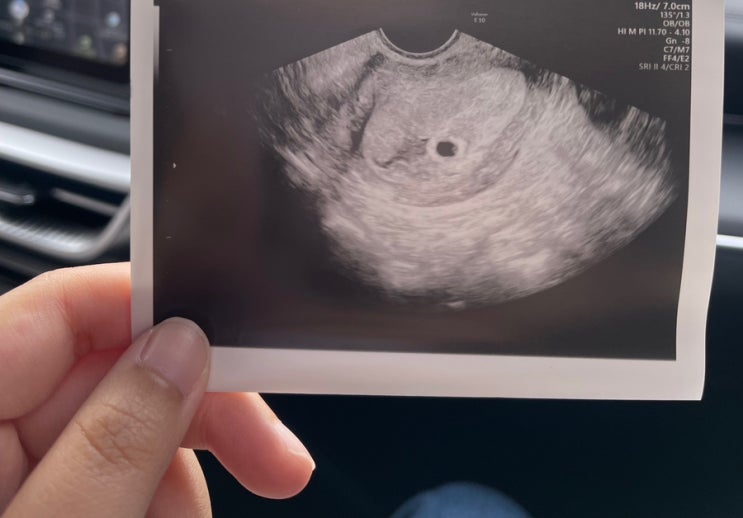

7주1일 심장소리, 아기 크기

지난 주 6주 1일 때 처음 심장소리를 들었다. 아마 103bpm이었는데 일주일 후인 오늘 가보니 심장박동수가 ...